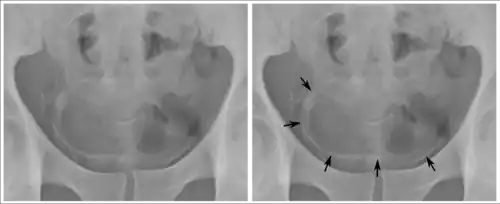

Inflammation and infection

Calcifications on bladder wall caused by urinary schistosomiasis

Cystitis refers to infection or inflammation of the bladder. It commonly occurs as part of a urinary tract infection.[25] In adults, it is more common in women than men, owing to a shorter urethra. It is common in males during childhood, and in older men where an enlarged prostate may cause urinary retention.[25] Other risk factors include other causes of blockage or narrowing, such as prostate cancer or the presence of vesico-ureteric reflux; the presence of outside structures in the urinary tract, such as urinary catheters; and neurologic problems that make passing urine difficult.[25] Infections that involve the bladder can cause pain in the lower abdomen (above the pubic symphysis, so called "suprapubic" pain), particularly before and after passing urine, and a desire to pass urine frequently and with little warning (urinary urgency).[25] Infections are usually due to bacteria, of which the most common is E coli.[25]

When a urinary tract infection or cystitis is suspected, a medical practitioner may request a urine sample. A dipstick placed in the urine may be used to see if the urine has white blood cells, or the presence of nitrates which may indicate an infection. The urine specimen may be also sent for microbial culture and sensitivity to assess if a particular bacteria grows in the urine, and identify its antibiotic sensitivities.[25] Sometimes, additional investigations may be requested. These might include testing the function of the kidneys by assessing electrolytes and creatinine; investigating for blockages or narrowing of the renal tract with an ultrasound, and testing for an enlarged prostate with a digital rectal examination.[25]

Urinary tract infections or cystitis are treated with antibiotics, many of which are consumed by mouth. Serious infections may require treatment with intravenous antibiotics.[25]

Interstitial cystitis refers to a condition in which the bladder is infected due to a cause that is not bacteria.[26][27]